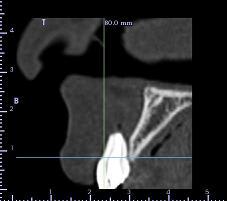

encore un ptit cas...sympa si on veut...car là j'ai besoin de l'expérience de ceux qui font çà souvent...

patient 17 ans...bientôt 18...

trauma dans l'enfance sur 11 et 21

pour la 21, çà va...mais la 11 est à bout de souffle...avec l'apex qui traverse la gencive vestibulaire...

veut un implant...forcément...mais là, faut une greffe...plutôt importante...

je pencherais plutôt pour un bloc fixé avec des vis d'ostéosynthèses...par contre, je suis pas chaud (et lui non plus) pour aller prélever au menton ou sur la branche montante...